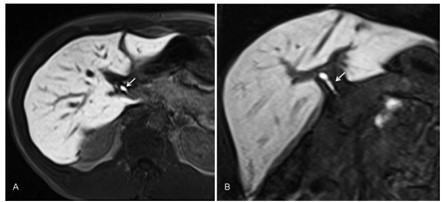

Son tumores poco frecuentes. Histológicamente están formados por hepatocitos bien diferenciados sin conductos biliares ni triada portal (tumor formado exclusivamente por hepatocitos). Pueden presentar áreas intralesionales de necrosis y de hemorragia. Es más frecuente en las mujeres (90%) que toman anticonceptivos orales y en hombres que toman esteroides anabólicos, así como en pacientes con enfermedades por depósito (glucogenosis tipo 1 o diabetes).

El aspecto de los adenomas en RM es variable ya que sus características pueden cambiar dependiendo de su contenido de grasa, presencia de hemorragia o fibrosis. Sin embargo, en general se presentan como masas hipointensas en T1, pero pueden tener áreas hiperintensas por presencia de sangre o de grasa.

En T2 son por lo general hiperintensos. Después de la inyección de contraste(18-24) paramagnético se observa un aumento de señal homogénea y muy precoz. La heterogeneidad de la señal es producto del amplio rango de cambios patológicos en el tumor, y es considerada una de las características más constantes del comportamiento del adenoma en RM. La mayor parte de los adenomas son solitarios (80%); entre 1% y 5% puede evolucionar a carcinoma hepatocelular.

Actualmente los adenomas se clasifican en tres subgrupos, dependiendo de su genotipo.(18) Es importante la clasificación para poder establecer su comportamiento, hallazgos por imagen, historia natural y, sobre todo, un riesgo variable de presentar complicaciones como hemorragia o malignización. Por ende, según sea el subtipo, también difiere el tratamiento. En la tomografía multicorte, en fase sin contraste, se observan como lesiones bien definidas, isodensas o ligeramente hipo o hiperdensas con respecto al parénquima (Anexo 23). Pueden presentar una densidad heterogénea o áreas de hemorragia.

En las fases dinámicas, tras la administración de medio de contraste,(18-24) son lesiones hipervasculares, ya que muestran importante reforzamiento en fase arterial. En las fases venosas portal y tardía se pueden diferenciar según el subtipo como: adenoma inflamatorio: persistencia del reforzamiento; adenoma HNF1A mutado: que se observa isodenso con respecto al parénquima normal; beta catenina mutada: que es hipervascular en fase arterial con lavado del medio de contraste similar al carcinoma hepatocelular.(18-20-24)